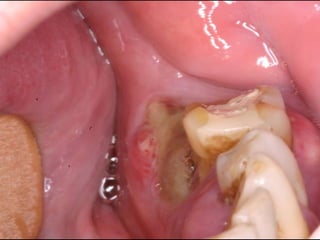

Granuloma (Lesão) Periférico de Células Gigantes A excisão cirúrgica deve ser antecedida de exame radiográfico, pois lesão não completamente removida e/ou com infiltração óssea, pode recorrer

Granuloma (Lesão) Periféricode Células Gigantes A excisão cirúrgica deve ser antecedida de exame radiográfico, pois lesão não completamente removida e/ou com infiltração óssea, pode recorrer

Exame complementares RadiografiaPanorâmica; Radiografia Oculsal; Teste de Vitalidade; Punção Exploratória; Biópsia incisional.

Teste de VitalidadeDente 43: Negativo Dentes 42,44 e 45: Positivo.